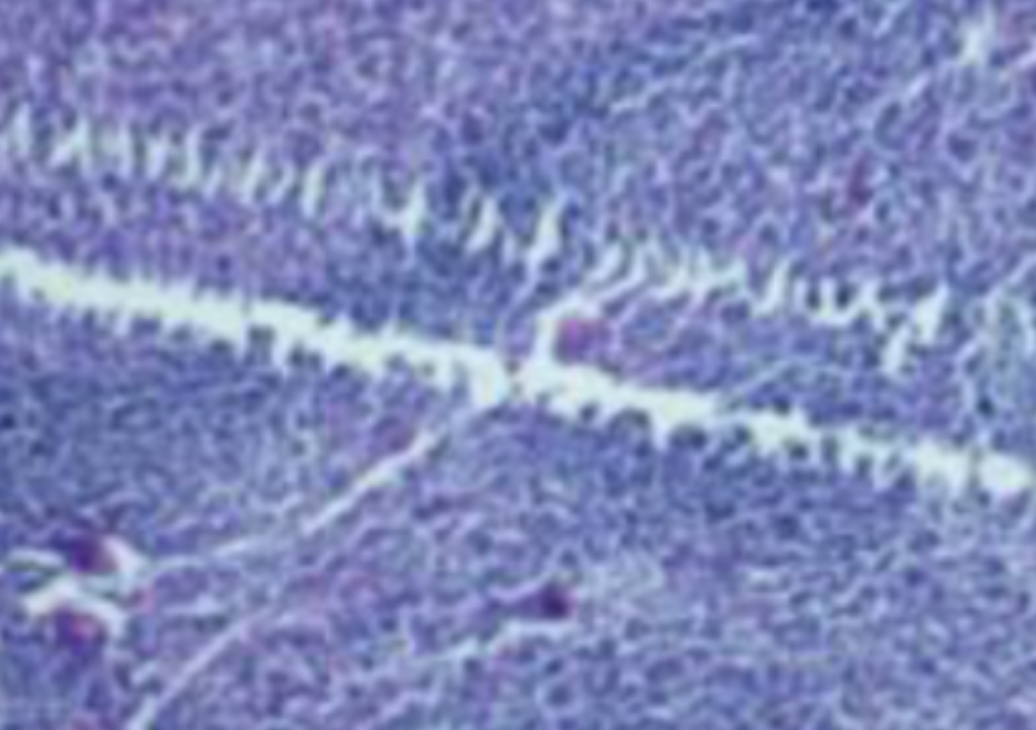

HE染色,全称苏木精-伊红染色法(Hematoxylin and Eosin staining),是最常见的组织切片染色技术之一,用于在显微镜下观察和分析组织或细胞的结构和形态。虽然HE染色是最常见且最基础的染色技术之一,😭但在实验过···

HE染色,全称苏木精-伊红染色法(Hematoxylin and Eosin staining),是最常见的组织切片染色技术之一,用于在显微镜下观察和分析组织或细胞的结构和形态。

虽然HE染色是最常见且最基础的染色技术之一,😭但在实验过程中,很容易出现各种情况导致染色切片质量参差不齐。所以,小编根据以往实验经验,给大家整理归纳出了15个HE染色中的常见问题,还包含问题原因分析以及解决方法哦~